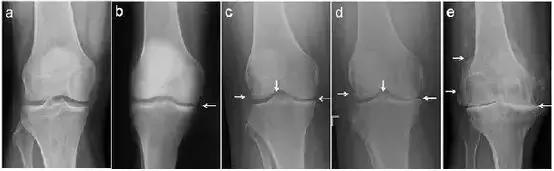

经常会遇到有人发现自己“关节疼、肿”,到医院拍片,诊断为“滑膜炎”(图1 a,b)、“骨质增生”(图1 c,d,e),还有诊断为“关节炎”的(图1 d,e)。那到底是那种病?我们对这几种病名分别了解一下。

图1:膝关节的各种X线拍片表现

从上可见,早期的(骨)关节炎就是滑膜炎。因为在常规X线片上无法观察到明显的关节周围骨质增生(即骨赘形成),或关节间隙变窄(图1c,1d,1e),因此被称之为“滑膜炎”。

患者关节肿痛,拍片子后看到报告单上描述的“骨质增生”,同时观察到X线片上关节(股骨或胫骨)周缘或髁间棘处增生的骨质(图1c,1d,1e左侧和中间白箭头),就断定自己得了“骨质增生”(有了“骨刺”)。

从前面我们可以知道,过度活动或年龄增大会造成关节磨损。轻度的关节损伤会造成“滑膜炎”;重度的关节损伤或年龄增大造成关节磨损会导致“退行性骨关节炎”,也就是常说的“关节炎”(图1c,1d,1e)。

6.对于晚上疼痛,难以入睡;以及因为关节疼痛无法出门,生活质量极差的骨关节炎患者(图1e)可以考虑关节置换。